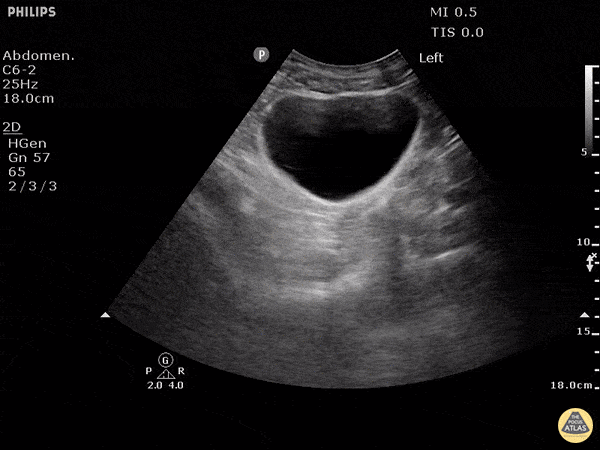

No free fluid is seen around or behind the bladder in this negative FAST. Dr. Justin Bowra